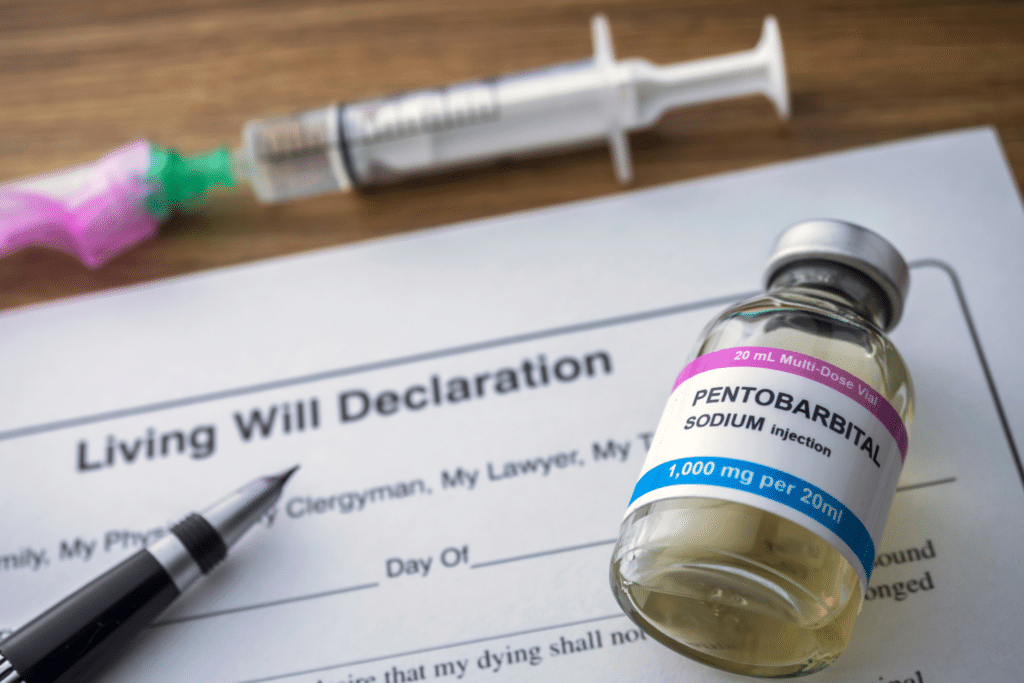

Press Release: ARPA Canada Calls On The Government To End MAiD Expansion

Press Release: Euthanasia should never be a solution for mental illness

January 26, 2023January 26, 2023 For immediate release OTTAWA, ON – The Liberal government ended 2022… Read More

Euthanasia can never be a solution for mental illness

Stories of MAiD

Runaway Euthanasia Train Feeling Some Drag

Assisted-death developments ‘deeply troubling’